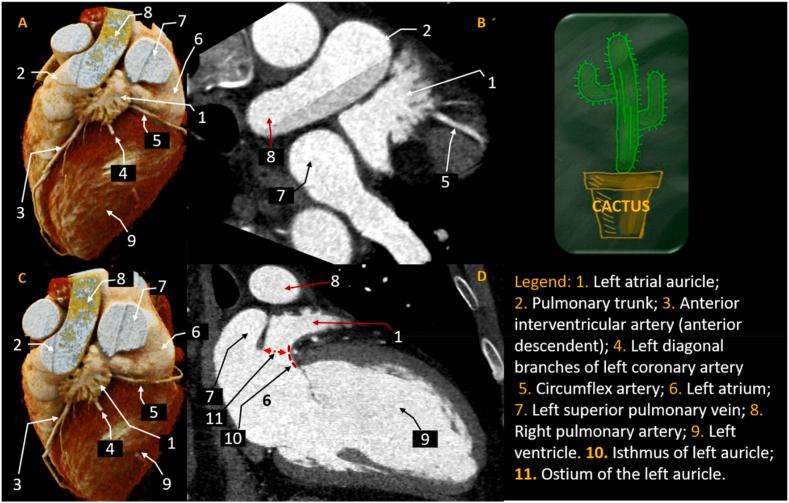

A highly-detailed anatomical study of left atrial auricle as revealed by in-vivo computed tomography.

The left atrial auricle (LAA) is the main source of intracardiac thrombi, which contribute significantly to the total number of stroke cases. It is also considered a major site of origin for atrial fibrillation in patients undergoing ablation procedures. The LAA is known to have a high degree of morphological variability, with shape and structure identified as important contributors to thrombus formation. A detailed understanding of LAA form, dimension, and function is crucial for radiologists, cardiologists, and cardiac surgeons. This review describes the normal anatomy of the LAA as visualized through multiple imaging techniques such as computed tomography (CT), magnetic resonance imaging (MRI), and echocardiography. Special emphasis is devoted to a discussion on how the morphological characteristics of the LAA are closely related to the likelihood of developing LAA thrombi, including insights into LAA embryology.